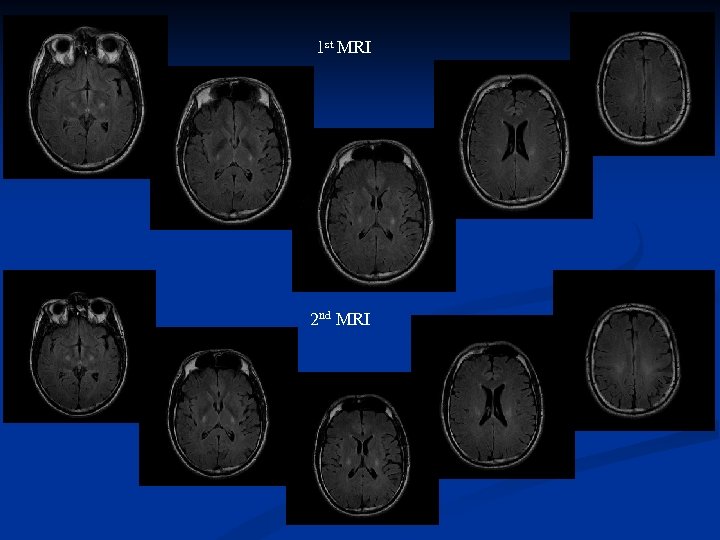

Follow up MRI was performed in nine ALS patients, four of which had distinct signal changes in the PLIC. Three of these patients deteriorated or developed definite ALS in the progress of the disease, thus changing diagnosting category according to the revised El Escorial criteria. The follow up examination disclosed that the increased T 2 FLAIR signal change got either more accentuated or more extended craniocaudally to the corona radiata/centum semiovale and the crus cerebri , demarkating the CST

Follow up MRI was performed in nine ALS patients, four of which had distinct signal changes in the PLIC. Three of these patients deteriorated or developed definite ALS in the progress of the disease, thus changing diagnosting category according to the revised El Escorial criteria. The follow up examination disclosed that the increased T 2 FLAIR signal change got either more accentuated or more extended craniocaudally to the corona radiata/centum semiovale and the crus cerebri , demarkating the CST

1 st MRI 2 nd MRI

1 st MRI 2 nd MRI

1 st MRI 2 nd MRI

1 st MRI 2 nd MRI